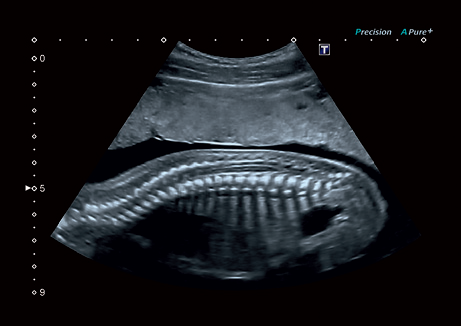

Система Aplio 300 – идеальный вариант для тех, кому нужна надежная и эффективная работа оборудования в ежедневной практике. Эта высокопроизводительная, универсальная и экономичная система предлагает получение качественных изображений с впечатляющей глубиной и детализацией в самых разных областях медицины.

• Превосходное качество визуализации и детализации анатомических структур для широкого спектра областей использования.

• Precision Imaging - технология получения изображений мелких деталей с четко очерченными границами и высокой однородностью

• Прецизионная визуализация (Precision Imaging) для послойного дифференцирования тканевых структур и высокой детализации;